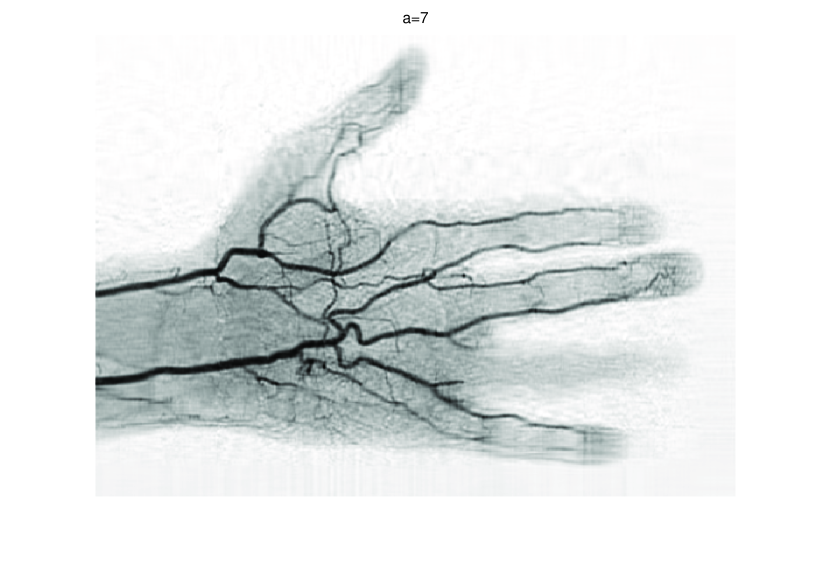

In this subsection, we demonstrate performances of ISVTA on image inpainting problems. The ISVTA is tested on some medical grace images (255×192255192255\times 192 Brain angiography image (BAI), 395×549395549395\times 549 Hand angiography image (HAI) and 419×400419400419\times 400 Intracranial venous image (IVI)). We use the SVD to obtain their approximated low-rank images with rank r=30,40,30𝑟304030r=30,40,30, respectively. Numerical results of ISVTA for theses low-rank image inpainting problems are reported in Table 5, 6, 7, 8.

Refer to caption

Figure 4: Original 395×549395549395\times 549 HAI and its approximation with rank 40.

Table 5, 6 show that ISVTA performs powerful in finding a low-rank matrix on image inpainting problems. Indeed, we could get an exact low-rank image by the ISVTA by choosing proper a𝑎a. Moreover, it is necessary to point out that our method does not work well for all a>0𝑎0a>0, and we can find that a=100𝑎100a=100 is not a good strategy for the low-rank IVI either SR=0.40SR0.40\mathrm{SR}=0.40 or SR=0.50SR0.50\mathrm{SR}=0.50. The numerical results of ISVT, SVTA and SVPA compared in Table 5, 6, 7, 8, 9, 10 under same circumstance show that the ISVT algorithm performs far more better than ISTA and SVPA on image inpainting problems for some proper a>0𝑎0a>0.